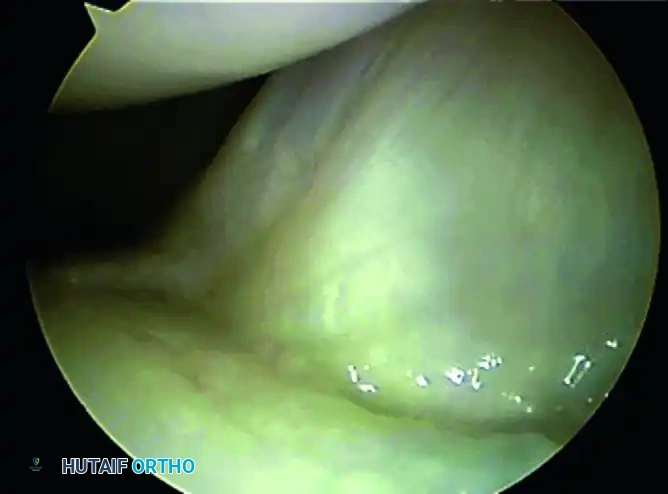

- Initial Orientation: Identify the palmar capsule of the wrist (appearing as a thick, white, ligamentous curtain) and the distal radial articular concavity inferiorly.

- Scaphoid and Scapholunate Interval: Move the arthroscope in the radial direction to identify the proximal margin of the scaphoid. Carefully evaluate the scapholunate (SL) articulation. The normal SL joint appears as a small, tight crease between the scaphoid and lunate, with intimate blending of the interosseous ligament with the adjacent articular cartilage.

- Dynamic Assessment: Use the probe from the 4-5 portal to palpate the SL ligament. Twist the probe to assess for abnormal widening or step-off, which would indicate a Geissler grade tear.

- Identifying Extrinsic Ligaments: Direct the 30-degree optic palmarly. Identify the stout palmar carpal ligaments. Moving from radial to ulnar, you will visualize the Radioscaphocapitate (RSC) ligament, the Long Radiolunate (LRL) ligament, and the vascular tuft of the Radioscapholunate (RSL) ligament. Use the probe to stress these ligaments and evaluate their structural integrity.

- TFCC Assessment: Evaluate the articular disc of the Triangular Fibrocartilage Complex (TFCC). The normal TFCC should be smooth, taut, and resilient. Use the probe to perform the "trampoline test"—pressing on the center of the disc. A normal TFCC will bounce back firmly. A soft or ballotable TFCC suggests a peripheral tear or detachment.

- Lunotriquetral Interval: Assess the lunotriquetral (LT) ligament for tears or step-offs, utilizing the probe to test for dynamic instability.